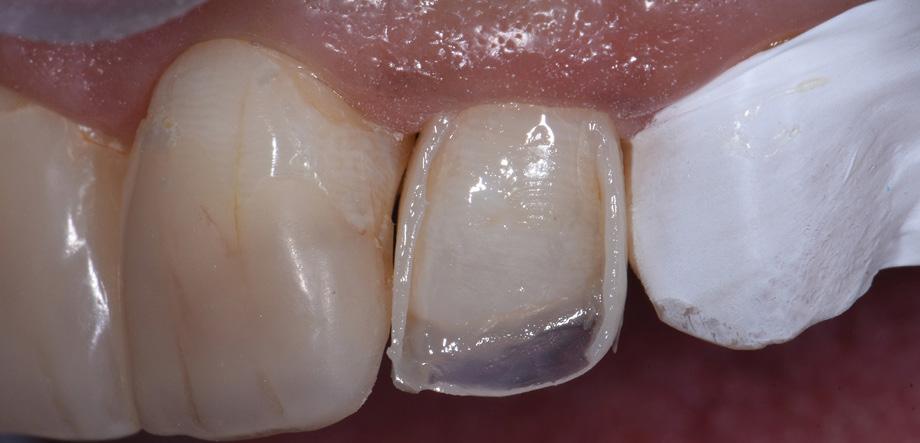

Class IV controlled layer concept utilising G-ænial™ A’CHORD in 3 shades

This case study presents the clinical management of a patient who presented with an existing failed anterior composite, requiring a Class IV direct composite replacement. The restoration aimed to achieve seamless integration with the natural dentition while restoring form and function.

3 - Completion of the Palatal Shelf and interproximal wall with the application of G-ænial™ A’CHORD composite, shade JE. The Interproximal wall was formed with the use of a plastic mylar strip and pull through technique to help develop an anatomical contour.

5 - A chromatic body shade, G-ænial™ A’CHORD shade A2 was then applied and extended beyond the bevel to mask the transition line. Internal anatomy in the incisal third was also sculpted and formed in this increment of composite resin. White tints, Essentia White Modifier (WM) was then utilised to accentuate the mamelons and to replicate similar characteristics present in the adjacent right central incisor.

4 - The dentine layer was then completed by the application of an opaque shade of G-ænial™ A’CHORD Shade AO2. This is to provide the correct opacity and “block out” effect of the final restoration.

Figure 1 - Pre-Operative presentation, exhibiting a failed direct composite restoration on the upper left central incisor (Tooth 21).

Figure 7 – 2-week review demonstrating the complete optical and functional G-ænial™ A’CHORD restoration on the tooth 21.

Figure 2 - Tooth surface cleaned and prepared with 37% Phosphoric Acid Etch prior to application of the adhesive with G-Premio BOND.

Figure 6 - A final translucent shade of G-ænial™ A’CHORD shade JE was then placed to bring the anatomy to full contour.